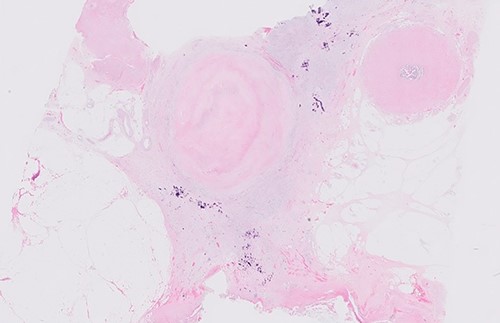

Postoperative histology demonstrated complete pathological response and an R0 resection (ypT0 N0(0/46) M0R0; Fig. 3). The patient proceeded to completion chemotherapy of 6 cycles of FOLFOX (folinic acid, fluorouracil and oxiliplatin) at 6 weeks postoperatively. He was then entered into a formal surveillance programme.